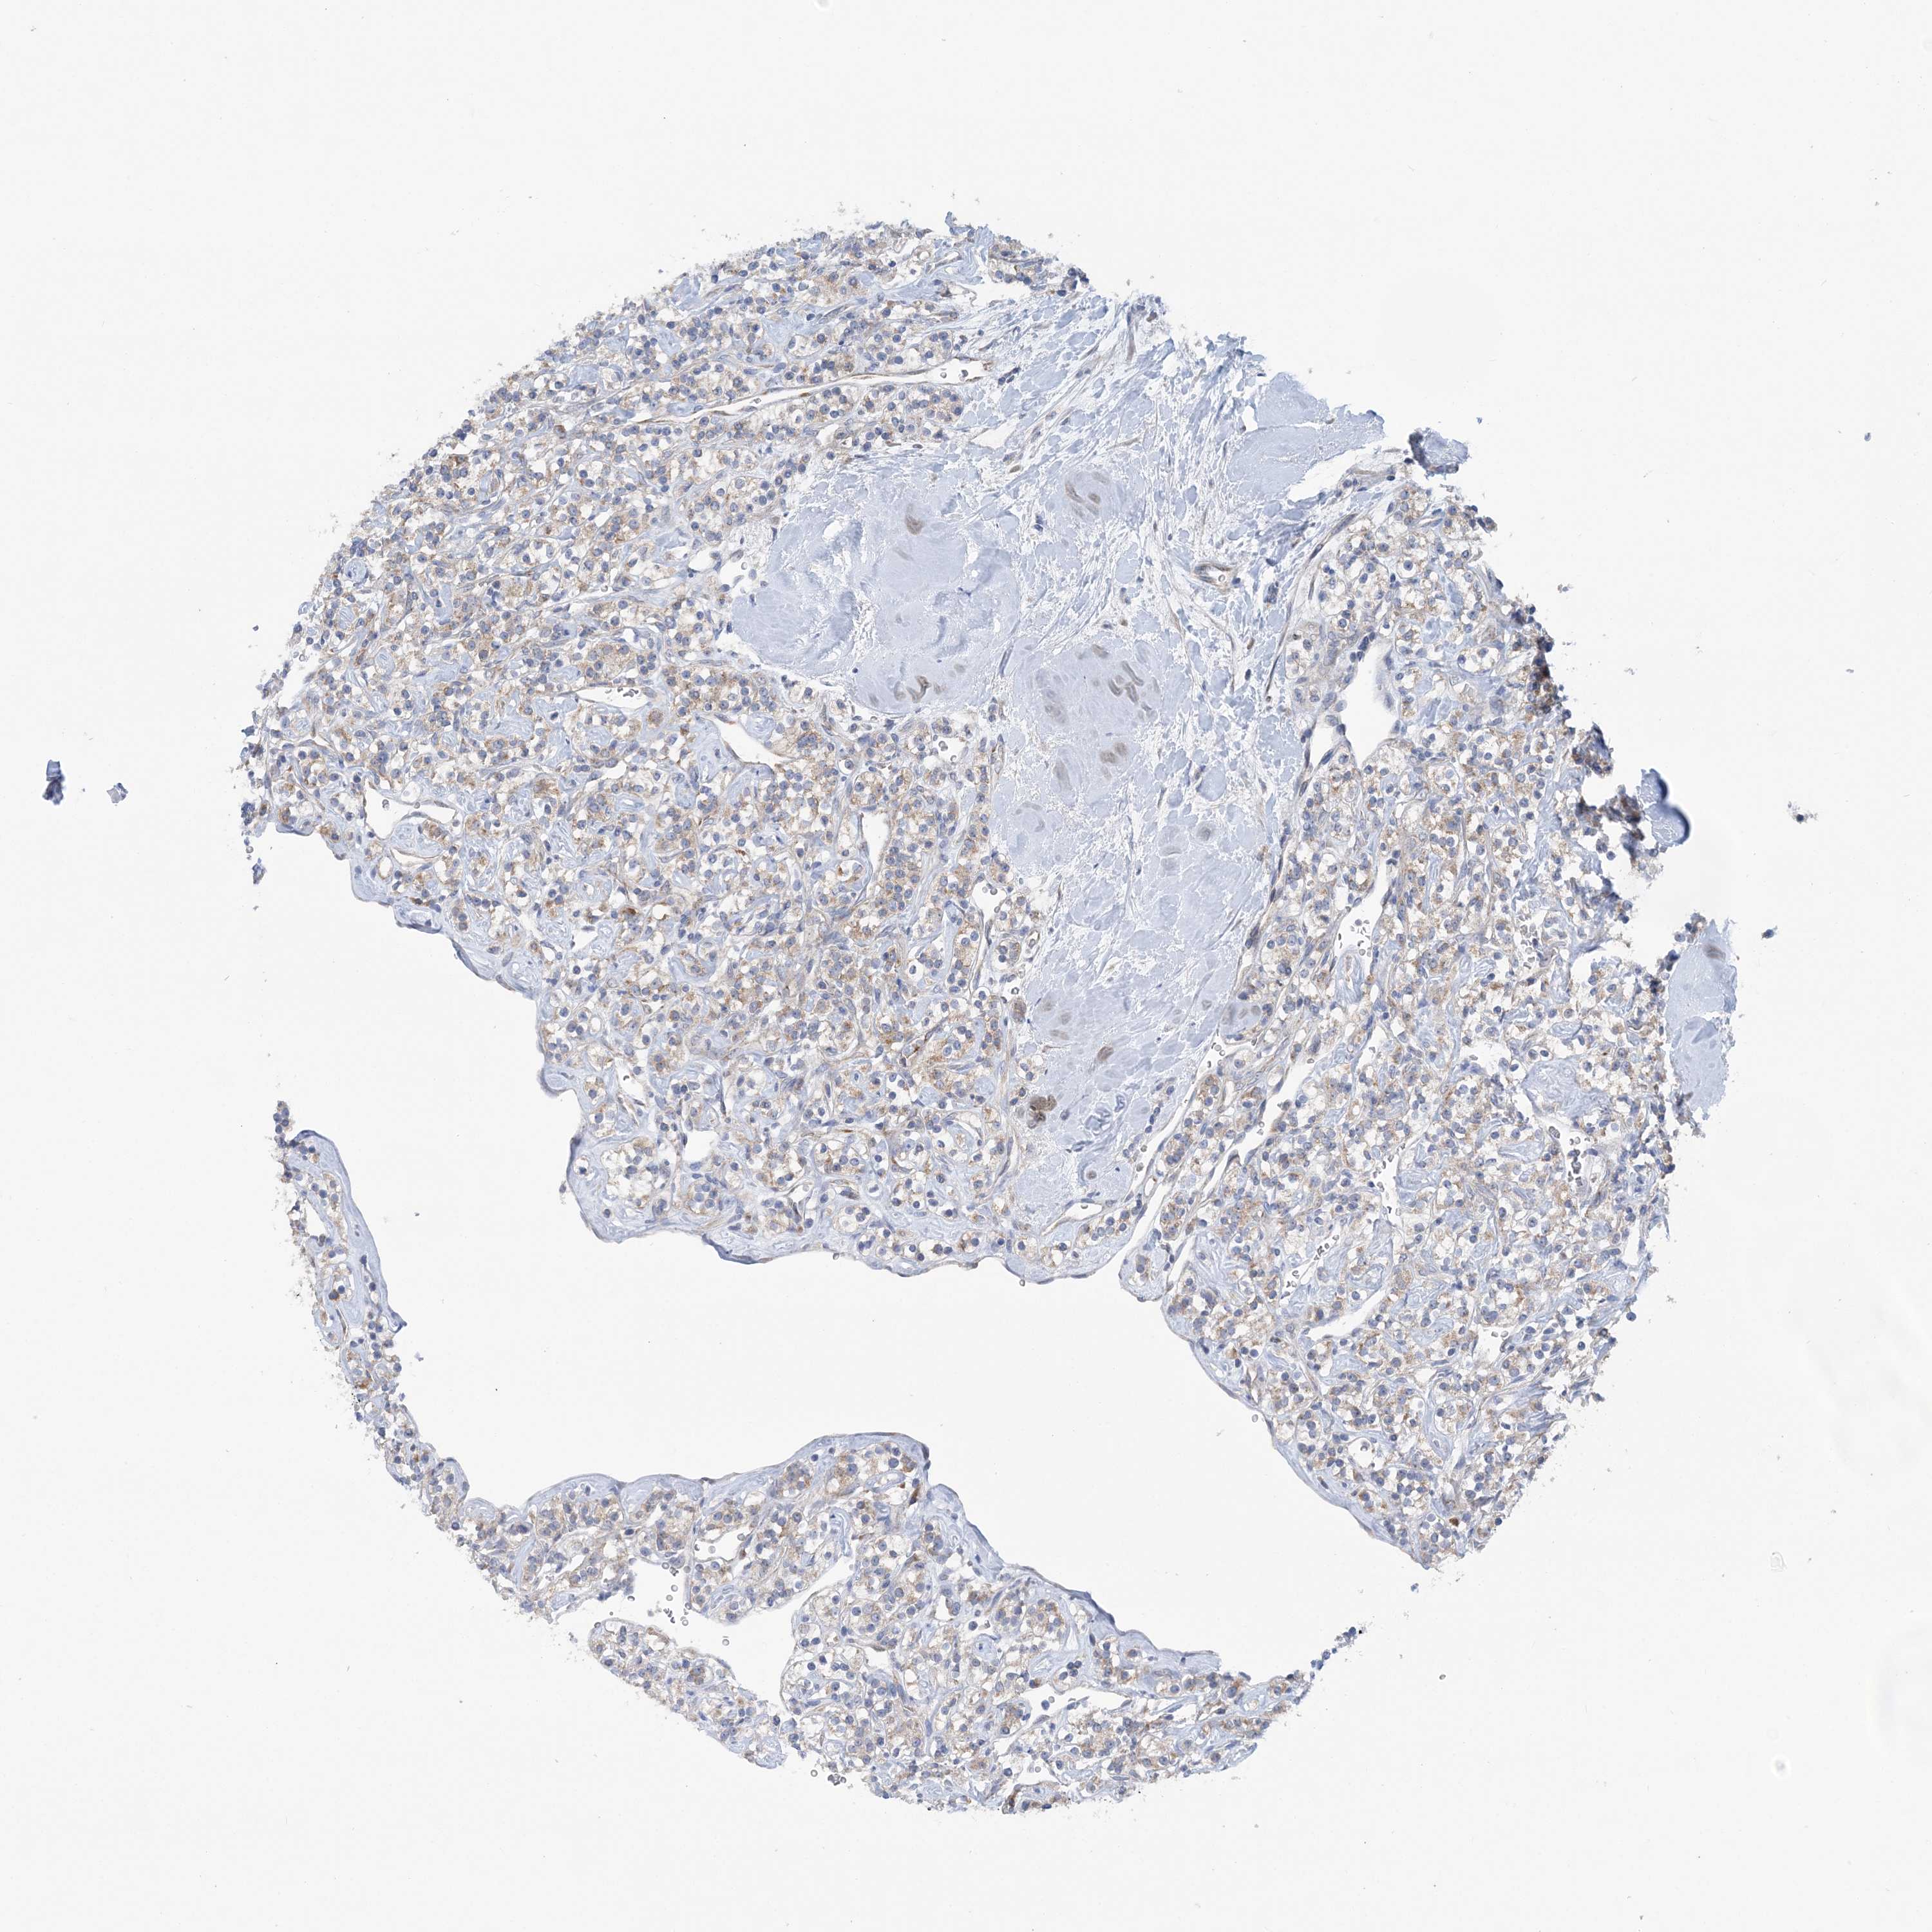

KIDNEY RENAL PAPILLARY CELL CARCINOMA (TCGA) - Interactive survival scatter ploti

The Survival Scatter plot shows the clinical status (i.e. dead or alive) for all individuals in the patient cohort, based on the same data that underlies the corresponding Kaplan-Meier plots. Patients that are alive at last time for follow-up are shown in blue and patients who have died during the study are shown in red.

The x-axis shows the expression levels (FPKM) of the investigated gene in the tumor tissue at the time of diagnosis. The y-axis shows the follow-up time after diagnosis (years). Both axes are complimented with kernel density curves demonstrating the data density over the axes. The top density plot shows the expression levels (FPKM) distribution among dead (red) and alive patients (blue). The right density plot shows the data density of the survived years of dead patients with high and low expression levels respectively, stratified using the cutoff indicated by the vertical dashed line through the Survival Scatter plot. This cutoff is automatically defined based on the FPKM cutoff that minimizes the p-score. The cutoff can be changed by dragging the vertical line or by entering a cutoff value in the square labeled "Current cut-off".

Under the Survival Scatter plot the p-score landscape (black curve; left axis) is shown together with dead median separation (red curve; right axis). Dead median separation is the difference in median mRNA expression between patients who have died with high and low expression, respectively. It is calculated as follows: median FPKM expression of dead patients with high expression - median FPKM expression of dead patients with low expression. This is intended to aid the user in visually exploring custom cutoffs and the associated p-scores and dead median separation.

Individual patient data is displayed and can be filtered by clicking on one or more of the category buttons on the top of the page. Categories describing expression level and patient information include: high, low, alive, dead, female, male and tumor stages. The scale of the x-axis can be toggled between linear and log-scale by clicking on the "x log" button. Mouse-over function shows TCGA ID, patient information and mRNA expression (FPKM) for each patient.

& Survival analysisi